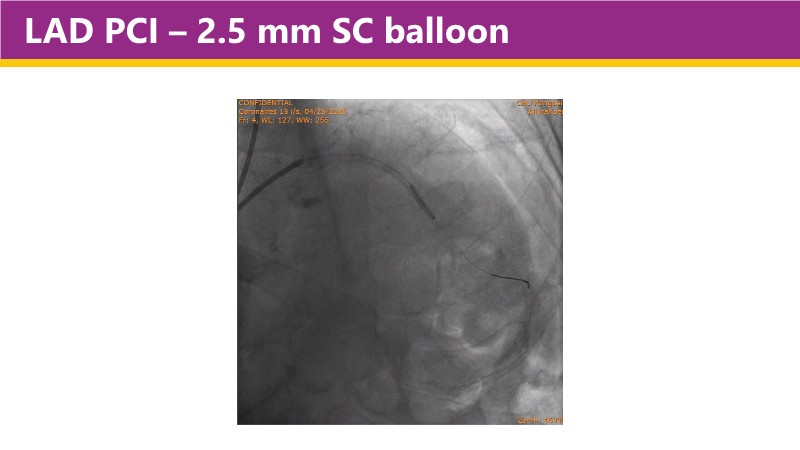

Learn how this technology works, review the supporting evidence, and follow step-by-step case examples demonstrating optimal stent expansion and an efficient calcium modification workflow in daily practice.